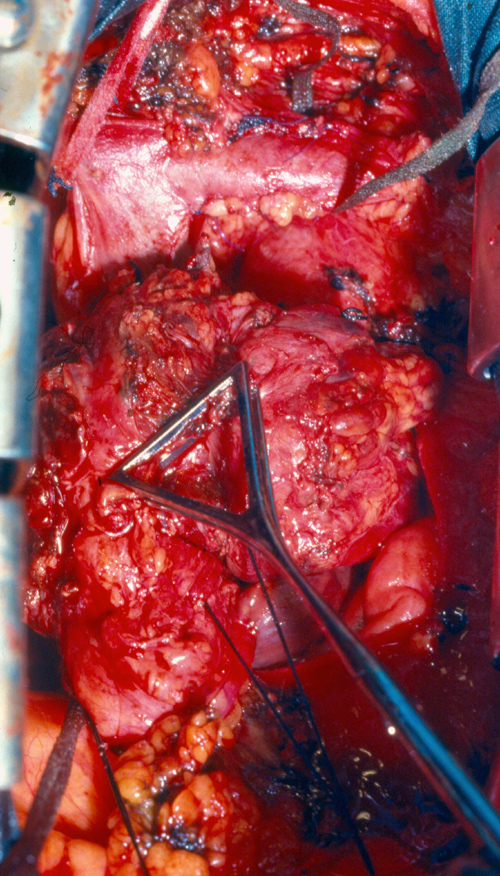

SVC replacement: replacement of the whole body of the SVC is the most frequent type of reconstruction (Figure 8). In patients with lung cancer, it is usually associated with right upper lobectomy or pneumonectomy; however, SVC reconstruction may be required during carinal pneumonectomy, sleeve lobectomy (Figure 9), and reconstructive procedures of the pulmonary artery[5]; the latter two should always be attempted if they help to avoid pneumonectomy. SVC replacement requires a tumor–free confluence of both brachiocephalic veins. The reconstruction is usually performed using a straight non-ringed PTFE graft (18 – 20 mm). An autologous or bovine pericardial tube could also be used (Figure 10). After proximal and distal clamping, the SVC is excised. The proximal anastomosis is performed first, using a 5-0 polypropylene suture, starting from the posterior aspect of the prosthesis or the tube of pericardium. The distal anastomosis is subsequently performed with the same technique. Before tying the distal suture line, the proximal clamp is gently released and deaeration is performed; afterwards, the distal clamp is released and knots are tied. After complete filling of the graft by blood, there should be no tension of the suture lines or torsion or kinking.